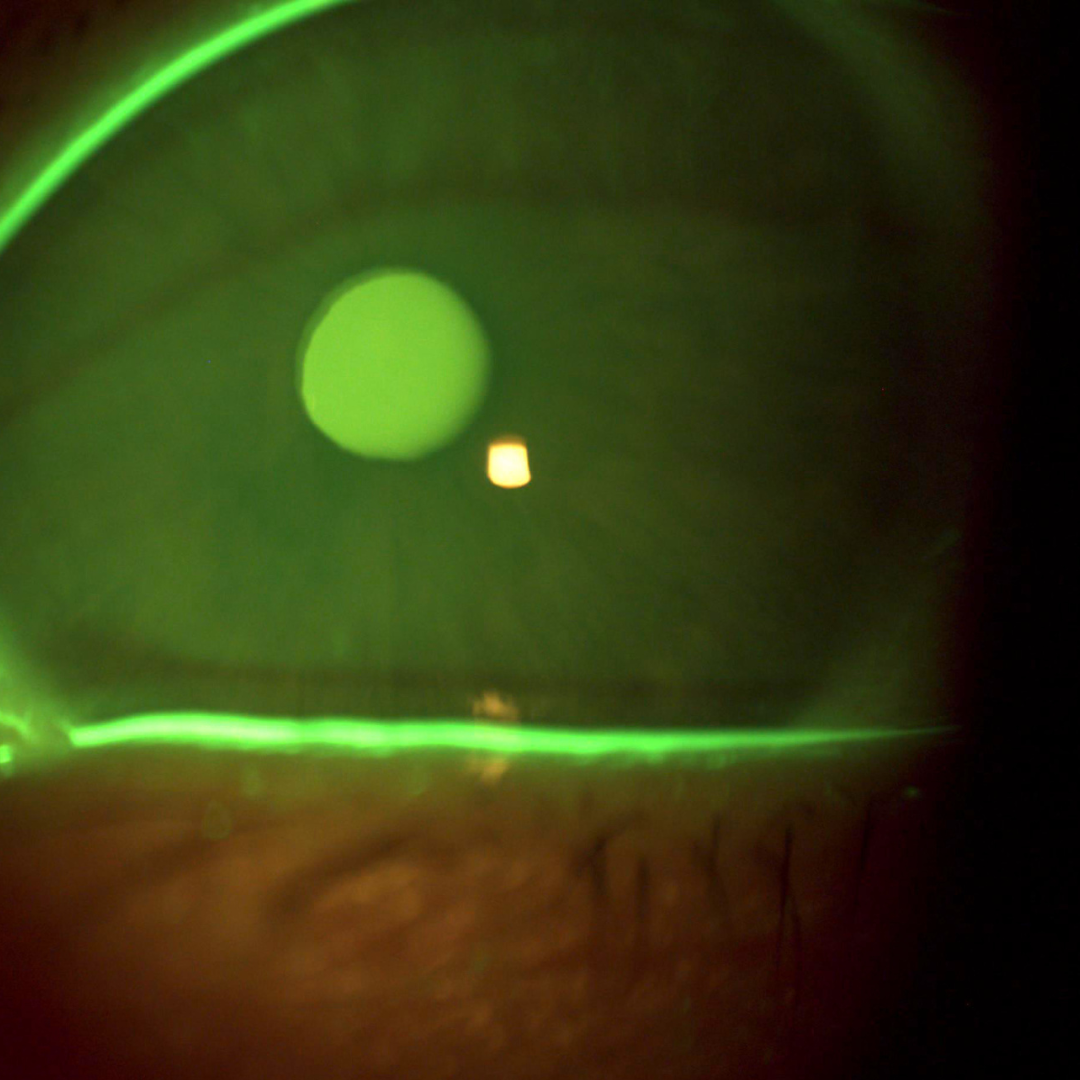

- FBUT (fluorescein tear break up time)

The video below shows software based fluorescein tear break up analysis in a patient with Sjogren’s disease.